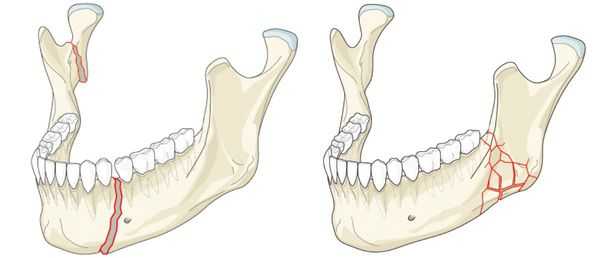

Перелом нижней челюсти — это нарушение целостности кости в одном или нескольких отделах.

Наиболее частой причиной возникновения перелома нижней челюсти является травматический фактор. В ряде случаев речь может идти о патологическом переломе из-за деструктивных процессов в костной ткани. [1] К таким патологическим процессам относятся:

- кисты челюстей;

- остеомиелит (гнойное воспаление костных тканей);

- онкологический процесс.

Кисты челюстей в основной массе протекают бессимптомно, медленно, но верно разрешая костную ткань. Часто патологический перелом вызвают радикулярные (корневые) и фолликулярные кисты. [2] Первые связаны с изменениями в периапикальных тканях одного или нескольких зубов, вторые являются результатом нарушения прорезывания зубов, чаще нижних зубов мудрости.

При онкологическом процессе нижняя челюсть может быть как первичным очагом, так и местом метастазирования посредством либо прорастания из близлежащих областей, либо распространением с током крови или лимфы. [3] Патологический процесс распространяется до тех пор, пока не разрушит костную ткань нижней челюсти до той стадии, в которой обычное пережевывание пищи может перевести к перелому.